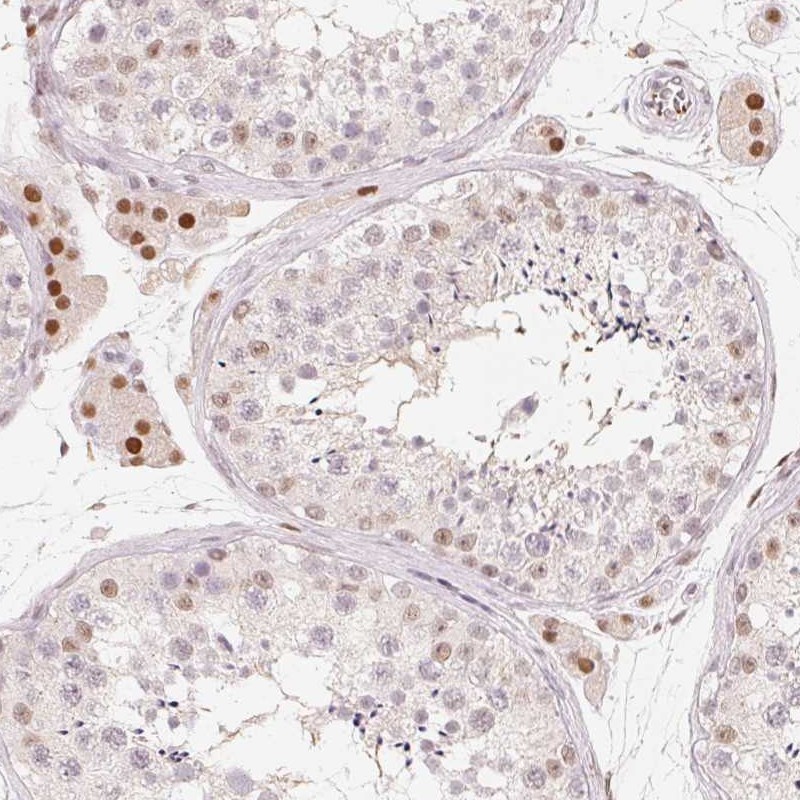

Immunohistochemical staining of human testis shows strong nuclear positivity in Leydig cells.